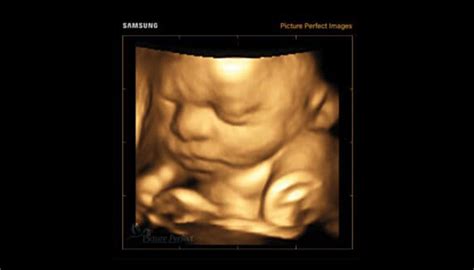

Ecografia 3D/4D în Morfologia Fetală

Adesea, ecografia 3D/4D este considerată sinonimă cu ecografia de morfologie fetală. Tehnica 3D/4D permite realizarea unui mulaj al diferitelor părți fetale, precum fața, mâinile, picioarele sau urechile. Prin reconstrucție tridimensională, pot fi evaluate anumite organe sau structuri fetale, cum ar fi inima, creierul sau palatul.

Este important de menționat că aceste mulaje nu au întotdeauna o utilitate directă în practica medicală și nu constituie neapărat baza pentru decizii de diagnostic.